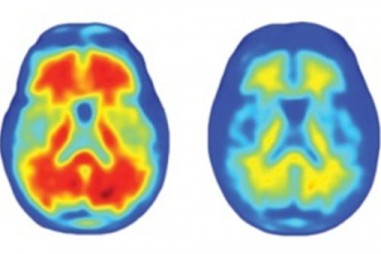

Các nhà khoa học cho biết có thể chẩn đoán tới 94% trường hợp mắc bệnh Alzheimer… 20 năm trước khi căn bệnh thực sự xuất hiện.

TNNN - Xét nghiệm máu mới có thể phát hiện những người mắc bệnh và có nguy cơ di truyền bệnh Alzheime sớm nhất là 20 năm, trước khi bắt đầu có dấu...